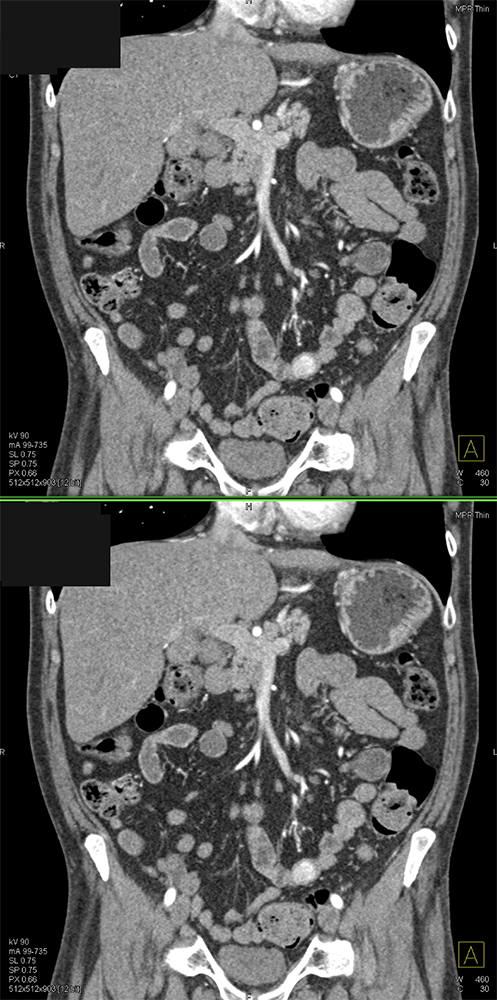

GIST Tumor Jejunum as the Cause of GI Bleeding ![]() |

![]() |

GI Bleed ![]() |